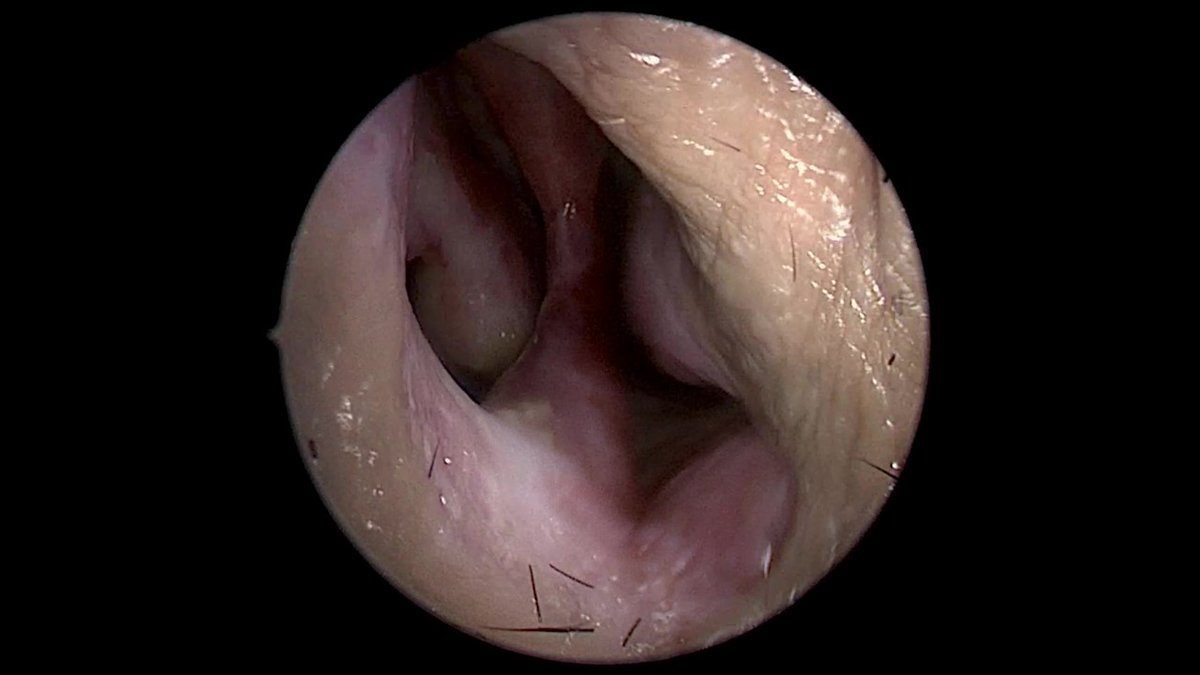

Just sharing the link to my case submission on MACS that is now available on the Cushing’s Hub website as an interactive case study. cushingshub.com/case-studies/a… @springermeded #Endotwitter